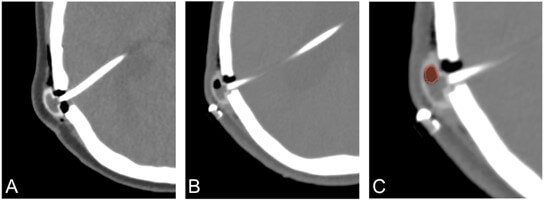

To measure the amount of air present inside brain ventricles and the VP shunt system, the software 3D Slicer 5.6.2 was used to segment the air bubbles. As shown in Figure 2, air appears hypodense on CT scans and can be easily delimited from surrounding structures. Regions with Hounsfield unit (HU) values below -1000 in the valve reservoir were considered to represent air and were segmented. All images were segmented by the same individual to minimize inter-user variability. The same measurement method was applied identically to both the case and control groups. The volume of air present in the ventricles and valve reservoir after initial shunt insertion (and after revision surgeries, if applicable) was determined. It was not possible to visualize the presence of air within the catheter components of the medical device, as these are radiopaque.